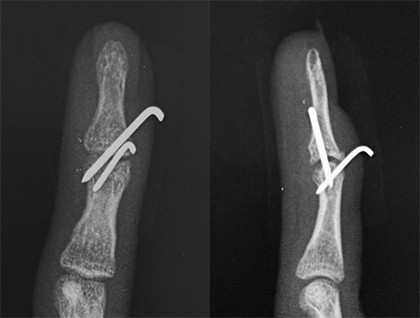

手術は局所麻酔を行い、金属ピンなどを用いて折れた骨や指の第一関節を固定します(図8,9,10,11)。装具を用いた固定を行った場合も手術を行った場合も、約6週間の終日固定が必要となります。また、固定期間中は装具の装着状況や指の状態を評価するため、定期的な通院が必要となります。

図10.右ひとさし指の骨性槌指

図11.3本の金属ピンで治療を行いました